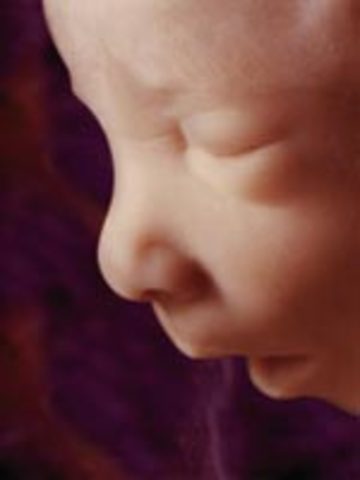

• week 12 Nails

week 12 Nails

the fetus finishes developing its facial profial and finishes developing its vocal chords. the fetus' brain is fuly formed and it feels pain, its pancreas will begin making insulin and the fetus will such on its fingers.

Fact: the fetus will cry silently occasionally in its mothers womb, the fetus has reached 2.5 inches and weighs 0.7 ounces